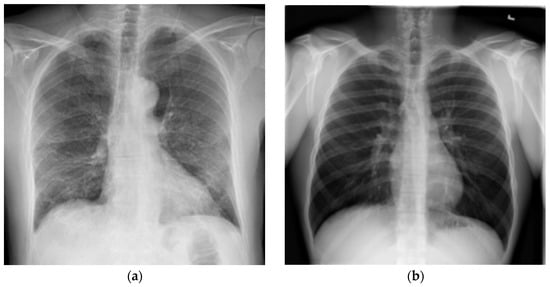

Images Use in COVID-19 Diagnosis